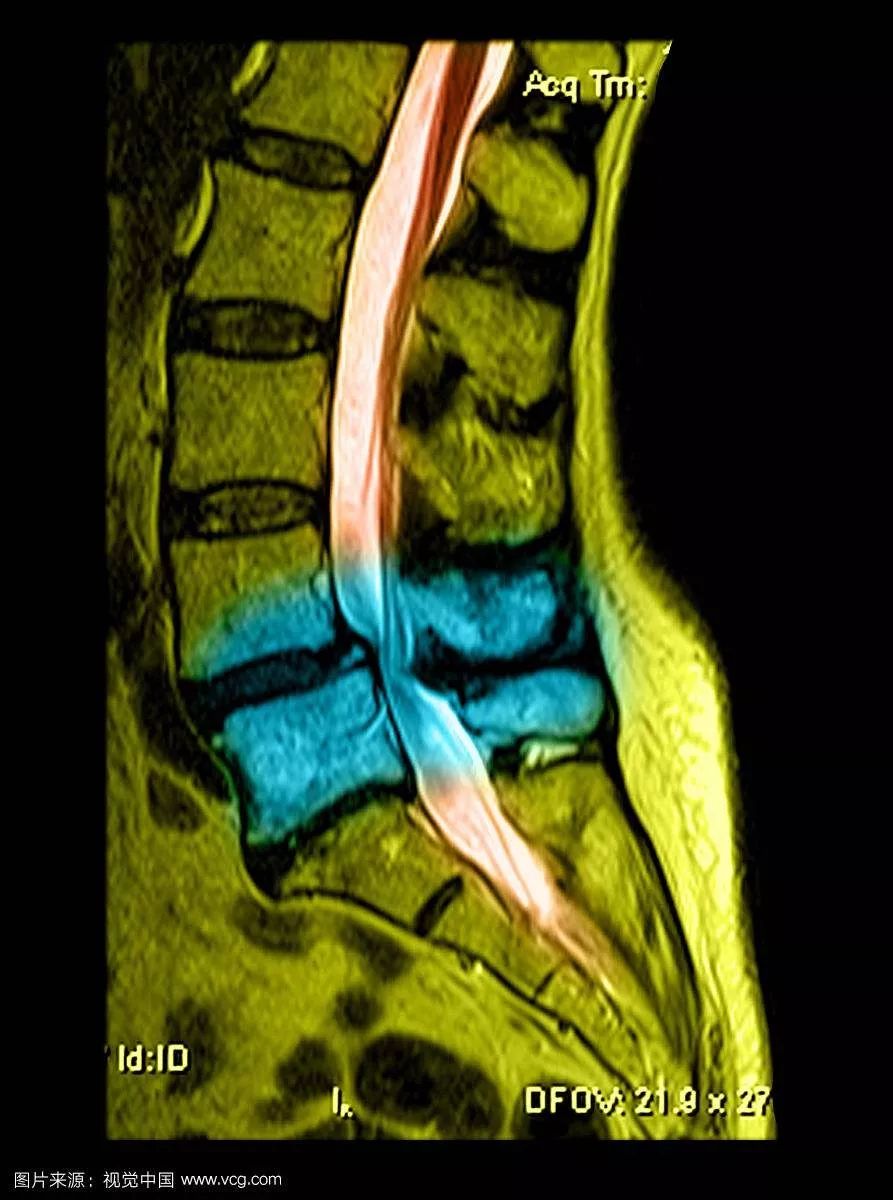

今天要给大家介绍的是82岁的盛老伯。孝顺镇某村人。时不时有腰痛不适的感觉已多年。近3多个月来,腰痛逐渐加重,并出现左下肢的麻木和疼痛,走路不方便,稍走远一点,左下肢就疼痛难忍,需要歇一会才能继续行走。为了减轻疼痛,必须弯腰走路。曾经用过许多药物及针灸治疗,但是不见好转。十多天前到仁康医院就诊,拍片及磁共振检查发现腰椎第四、第五节之间明显骨质增生,同时有椎间盘突出,椎管狭窄。由于神经压迫明显,只能通过手术,取除突出的椎间盘,扩大狭窄的椎管,才能解除症状。

术前的磁共振及X光片